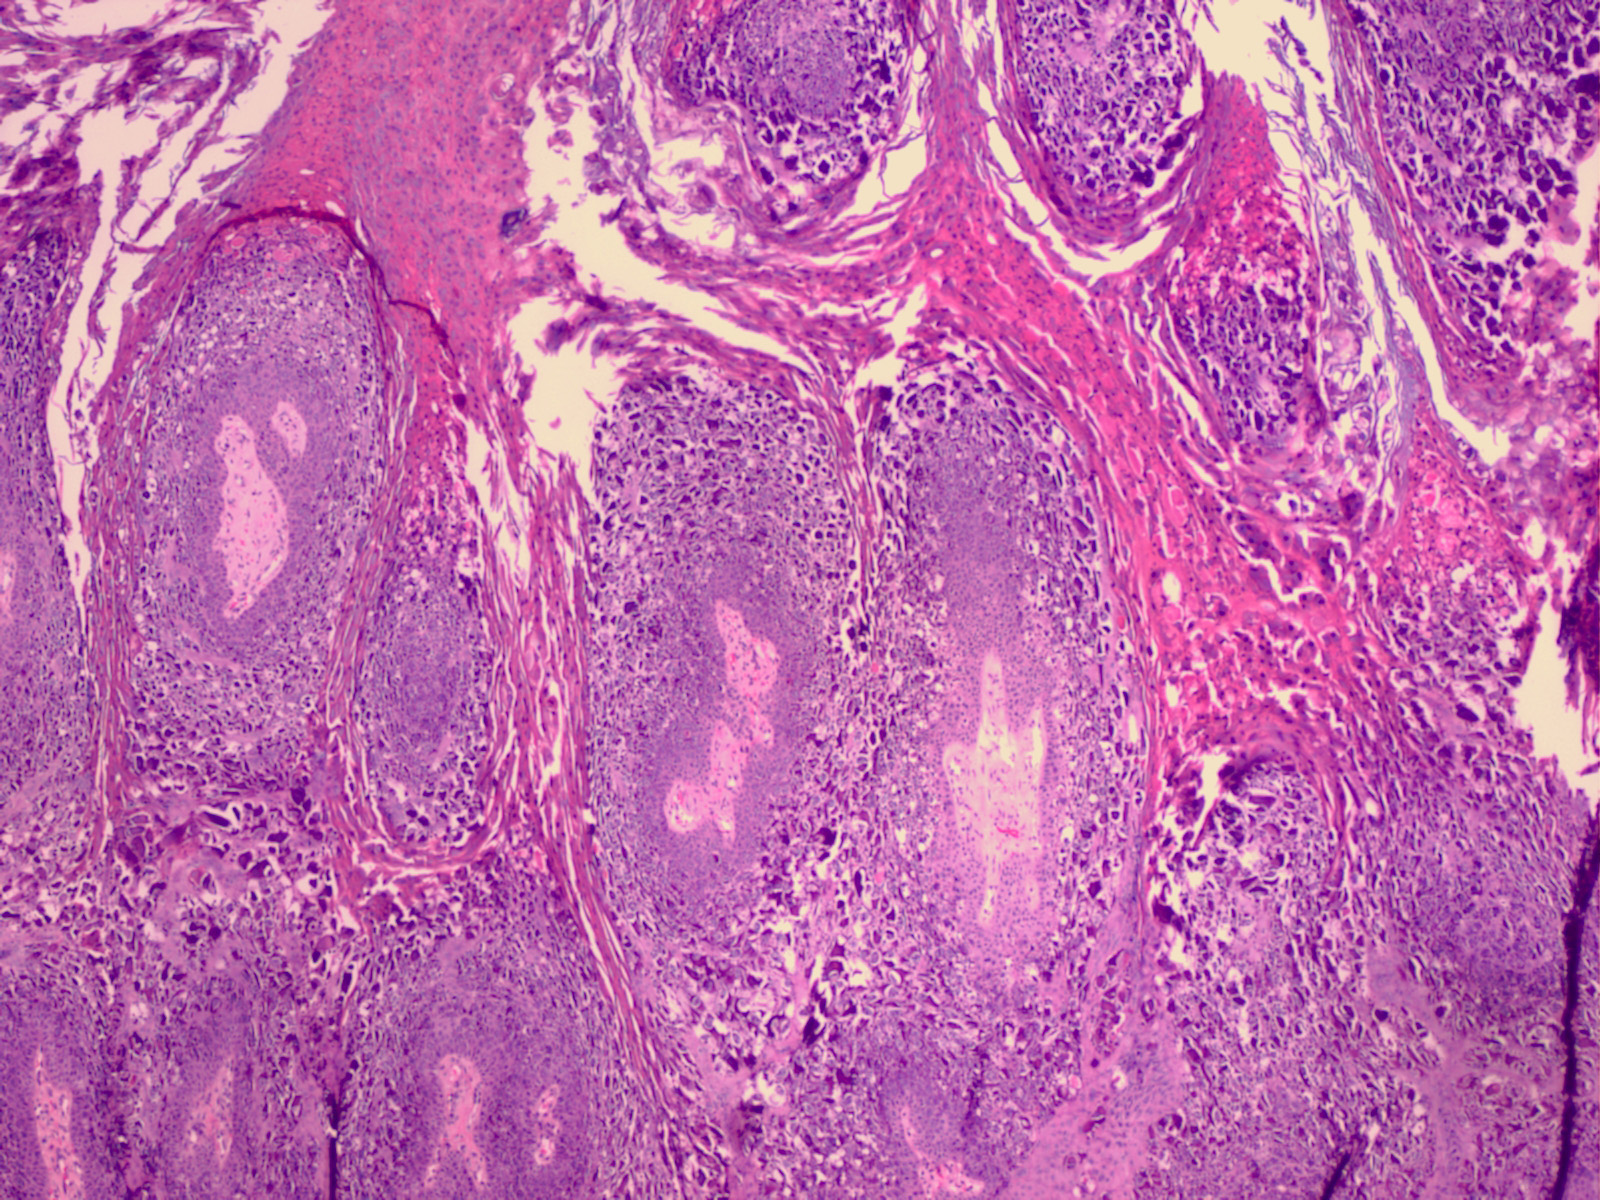

Verruca palmoplantaris = الثؤلول الراحي الاخمصي